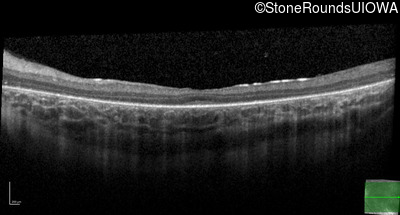

Age at visit: 12 years